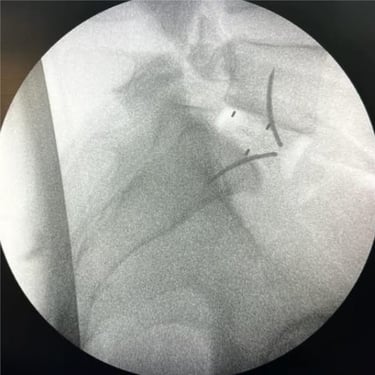

La cirugía ALIF (Anterior Lumbar Interbody Fusion), o Fusión Lumbar Intercorporal Anterior, es una técnica quirúrgica utilizada para tratar patologías de la columna lumbar como la degeneración discal, la inestabilidad vertebral o las hernias lumbares recurrentes. Mediante un abordaje anterior, se extrae el disco dañado y se coloca un injerto o caja intersomática que permite lograr la fusión estable entre las vértebras. Este procedimiento favorece una mejor restauración del espacio discal, alineación lumbar y preservación muscular. La cirugía ALIF es realizada por un equipo especializado en neurocirugía de columna, garantizando precisión y resultados funcionales óptimos.